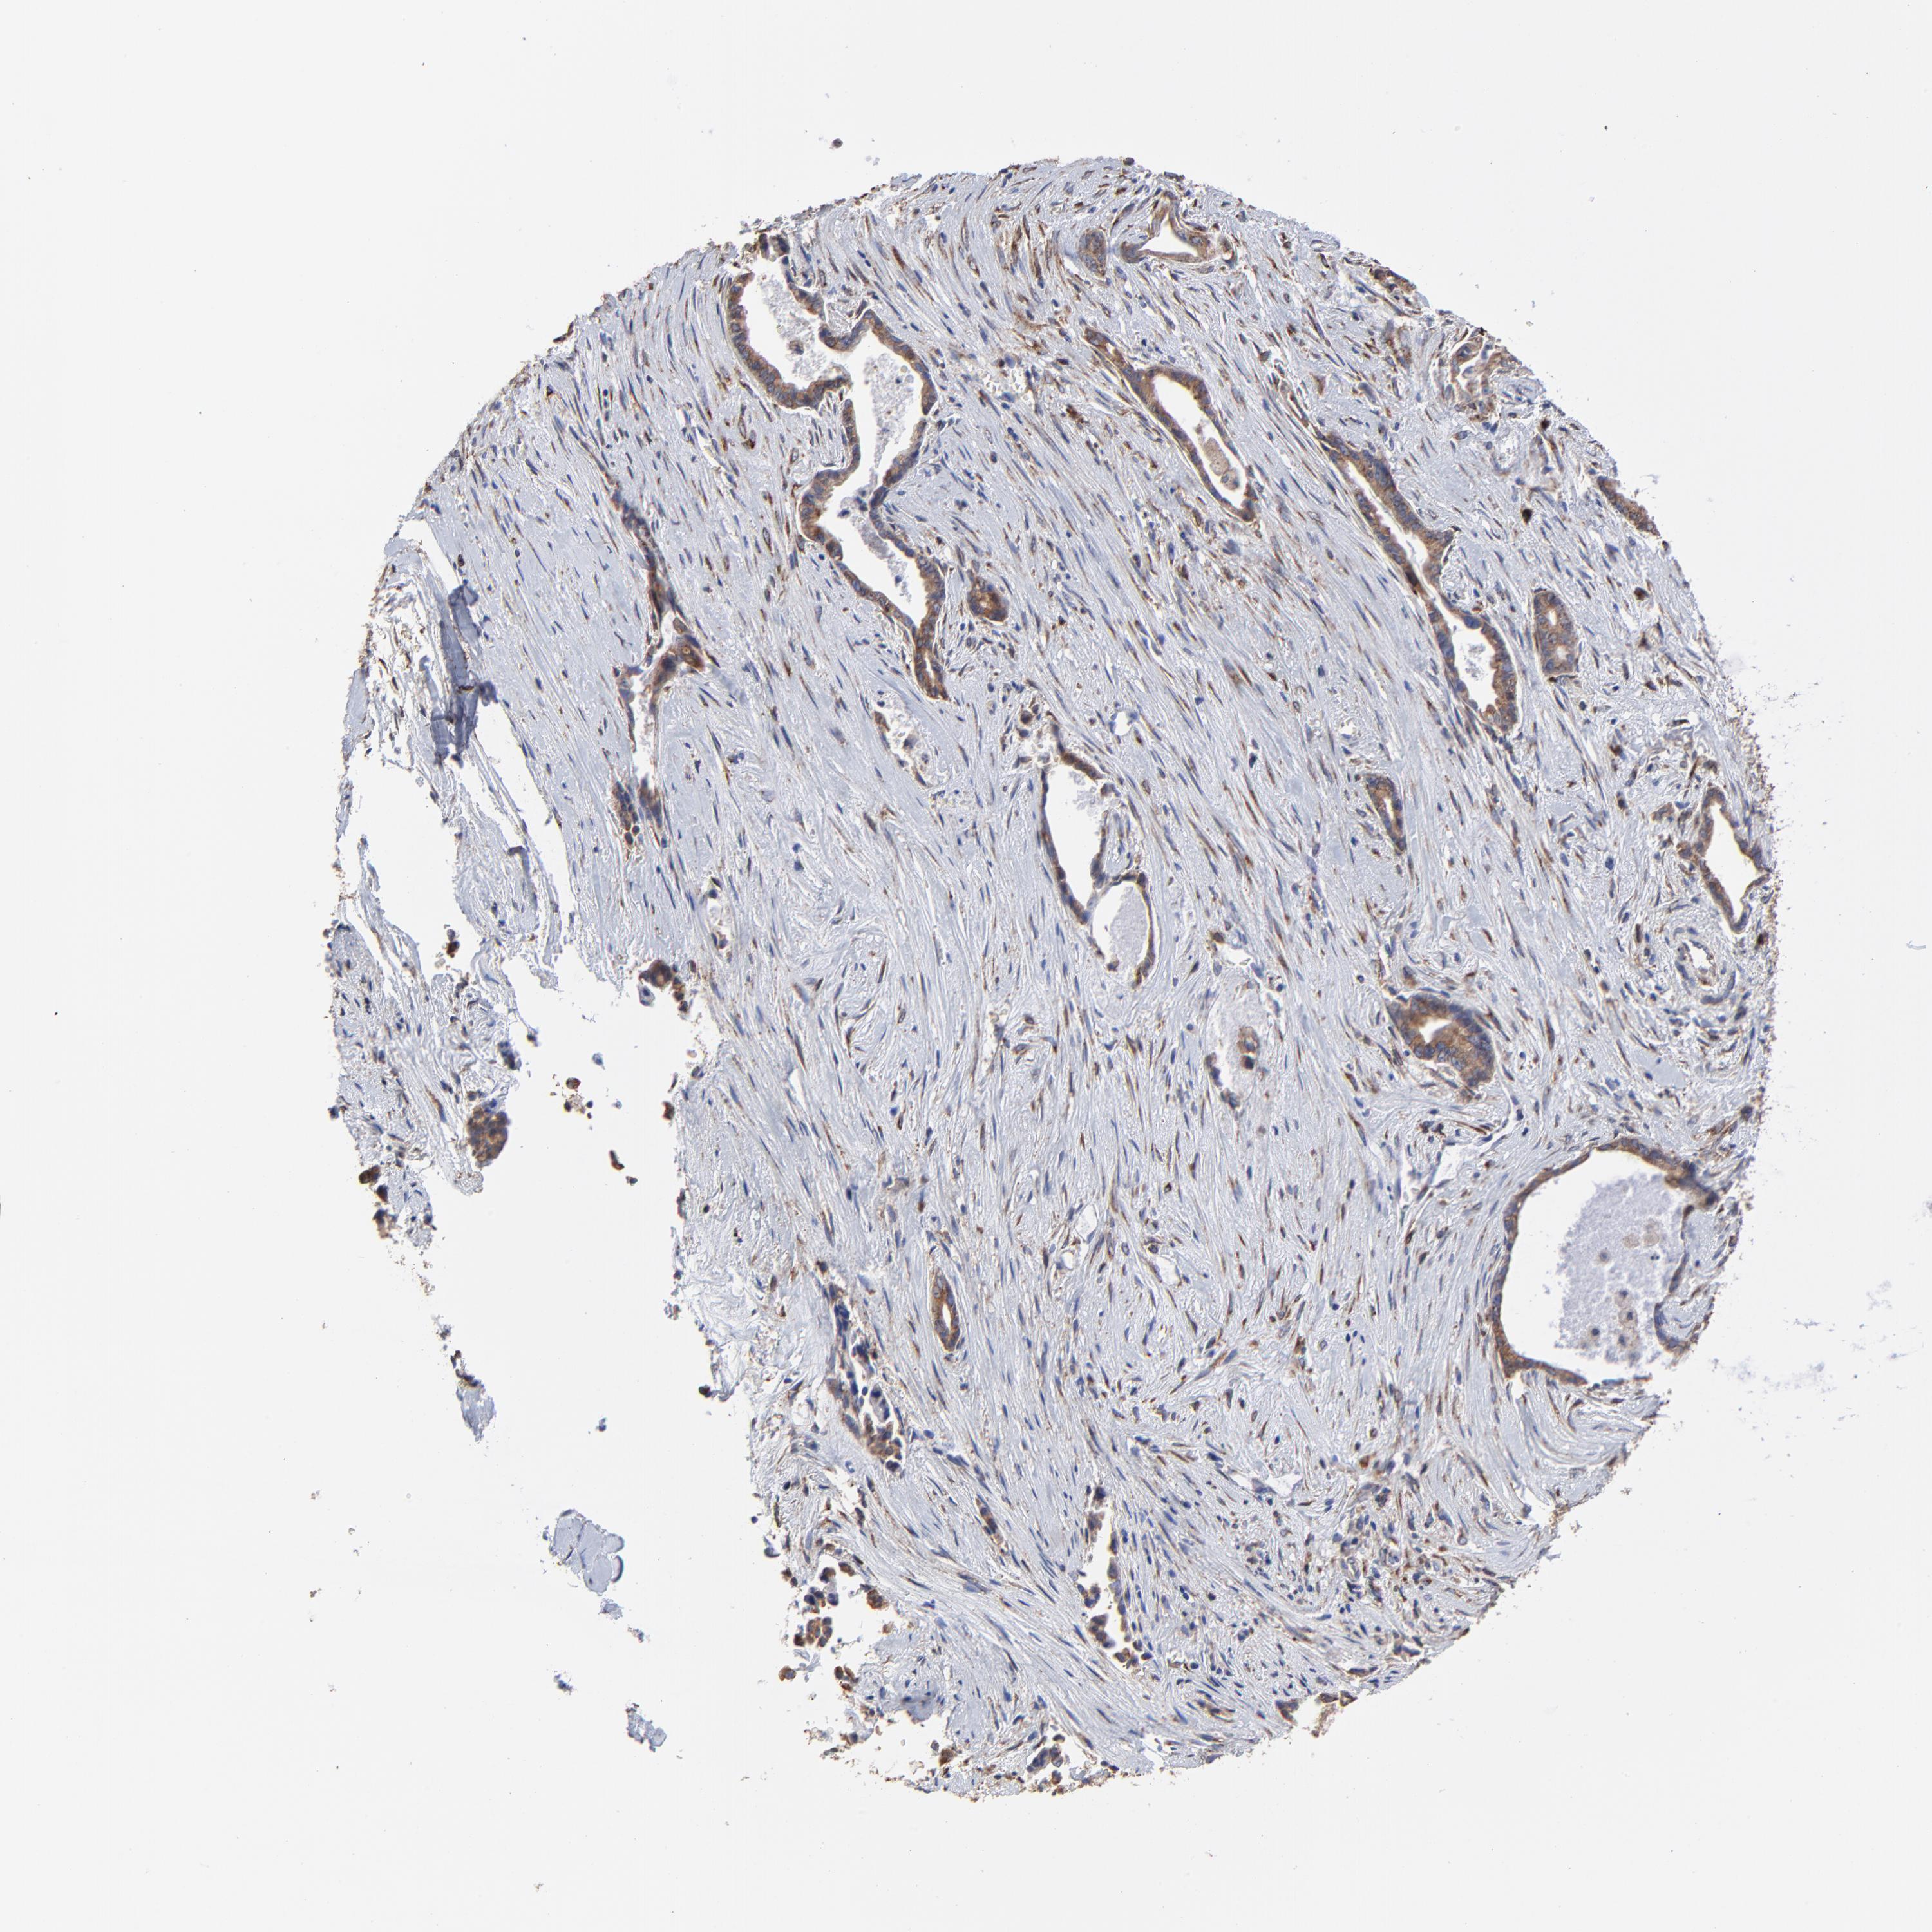

LIVER CANCER - Protein expressioni

A mouse-over function shows sample information and annotation data. Click on an image to view it in a full screen mode. Samples can be filtered based on level of antibody staining by selecting one or several of the following categories: high, medium, low and not detected. The assay and annotation is described here.

Note that samples used for immunohistochemistry by the Human Protein Atlas do not correspond to samples in the TCGA dataset.

Antibody stainingi

Antibody staining in the annotated cell types in the current human tissue is reported as not detected, low, medium, or high, based on conventional immunohistochemistry profiling in selected tissues. This score is based on the combination of the staining intensity and fraction of stained cells.

Each image is clickable and will lead to virtual microscopy that enables deeper exploration of all samples and also displays staining intensity scores, fraction scores and subcellular localization as well as patient and tissue information for each sample.

Antibody HPA002320

Antibody CAB037163

Staining

High

Medium

Low

Not detected

Intensity

Strong

Moderate

Weak

Negative

Quantity

>75%

75%-25%

<25%

None

Location

Nuclear

Cytoplasmic/membranous

Cytoplasmic/membranous,nuclear

Cholangiocarcinoma

Carcinoma, Hepatocellular, NOS